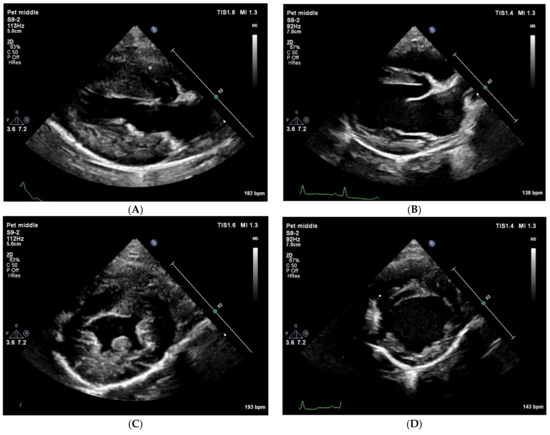

Next, an abdominal ultrasound examination was performed to investigate the abdominal aorta and the CVC. The abdominal aorta showed normal pulsed-wave Doppler flow pattern, but unexpectedly, it was located to the right of the CVC (Figure 2).

The CVC in the cranial abdomen showed an extreme aneurysm with a diameter up to 45 mm, with blood stasis to sluggish blood flow with spontaneous echo contrast in it (Figure 3). No thrombus was noted.

Figure 3. Two-dimensional grey-scale ultrasound images show an aneurysm of the azygos vein dorsal to the right kidney in longitudinal (A) and in cross section (B). In the vessel, spontaneous echo contrast is visible because of the blood stasis and sluggish flow. The images were obtained via the right lateral abdominal wall with the dog in left lateral recumbency. These findings suggest a severe venous obstruction downstream (i.e., cranial) to this location.

Figure 4. Two-dimensional grey-scale abdominal ultrasound images. (A) The great abdominal vessels in cross-section at the level of the liver obtained through an intercostal space from the right side with the dog in left lateral recumbency. To the left of the image is dorsal, to the right is ventral, to the top is right and to the bottom of the image is the left side of the dog. Dorsal and to the right of the aorta (round anechoic structure), an oval and equally large vascular structure is visible, compatible with an anatomical localization of a dilated (right) azygos vein. At the same time, no vessel can be seen at the location where the caudal vena cava is expected (ventral to the aorta, surrounded with liver tissue). (B) The left kidney displayed in a longitudinal image shows a moderately dilated renal pelvis (~1.7 cm). This finding is compatible with a unilateral ureteral compression or obstruction.